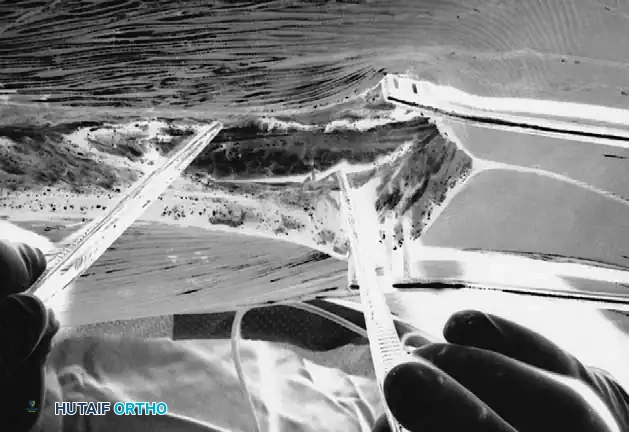

Rib Identification and Periosteal Stripping

- Palpation and Marking: Once the fascia is retracted laterally, palpate the ribs starting precisely at the apex of the deformity. Mark the apical rib with electrocautery. Symmetrical resection is planned, working distally and proximally one rib at a time. Usually, between four and six ribs are outlined for resection.

- Lateral Periosteal Stripping: Use a periosteal elevator to strip the periosteum off the superficial surface of the rib out to the lateral edge.

- Inferior Edge Stripping: Once the superficial periosteum is stripped to the side, use the elevator to carefully strip the periosteum and intercostal muscle attachments around the inferior edge of the rib.

- Anterior Stripping (The Danger Zone): With a curved Cobb elevator, strip the periosteum from the anterior (deep) aspect of the rib in a medial to lateral direction. This is the step where the pleura is most vulnerable and most likely to be entered. Keep the instrument firmly applied to the bone.

- Retractor Placement: Once the anterior aspect of the rib has been safely stripped, pass a Doyen rib retractor circumferentially from medial to lateral around the exposed rib to protect the underlying pleura.

- Medial Cut: Identify the most medial attachment of the rib to the transverse process. Pass a heavy rib cutter around the rib, pushing it as far medially as possible. Secure the rib segment with a towel clip or Kocher clamp. This prevents the sharp end of the rib from plunging downward through the pleura the moment it is cut. Cut the rib medially, keeping the blades of the cutter as parallel to the floor as possible to avoid leaving a sharp, downward-pointing spike.

- Lateral Cut and Resection Limits: Make the lateral cut. For a standard rib resection in a patient with a 55-degree right thoracic curve, approximately 2 cm of rib should be cut initially at the apex.